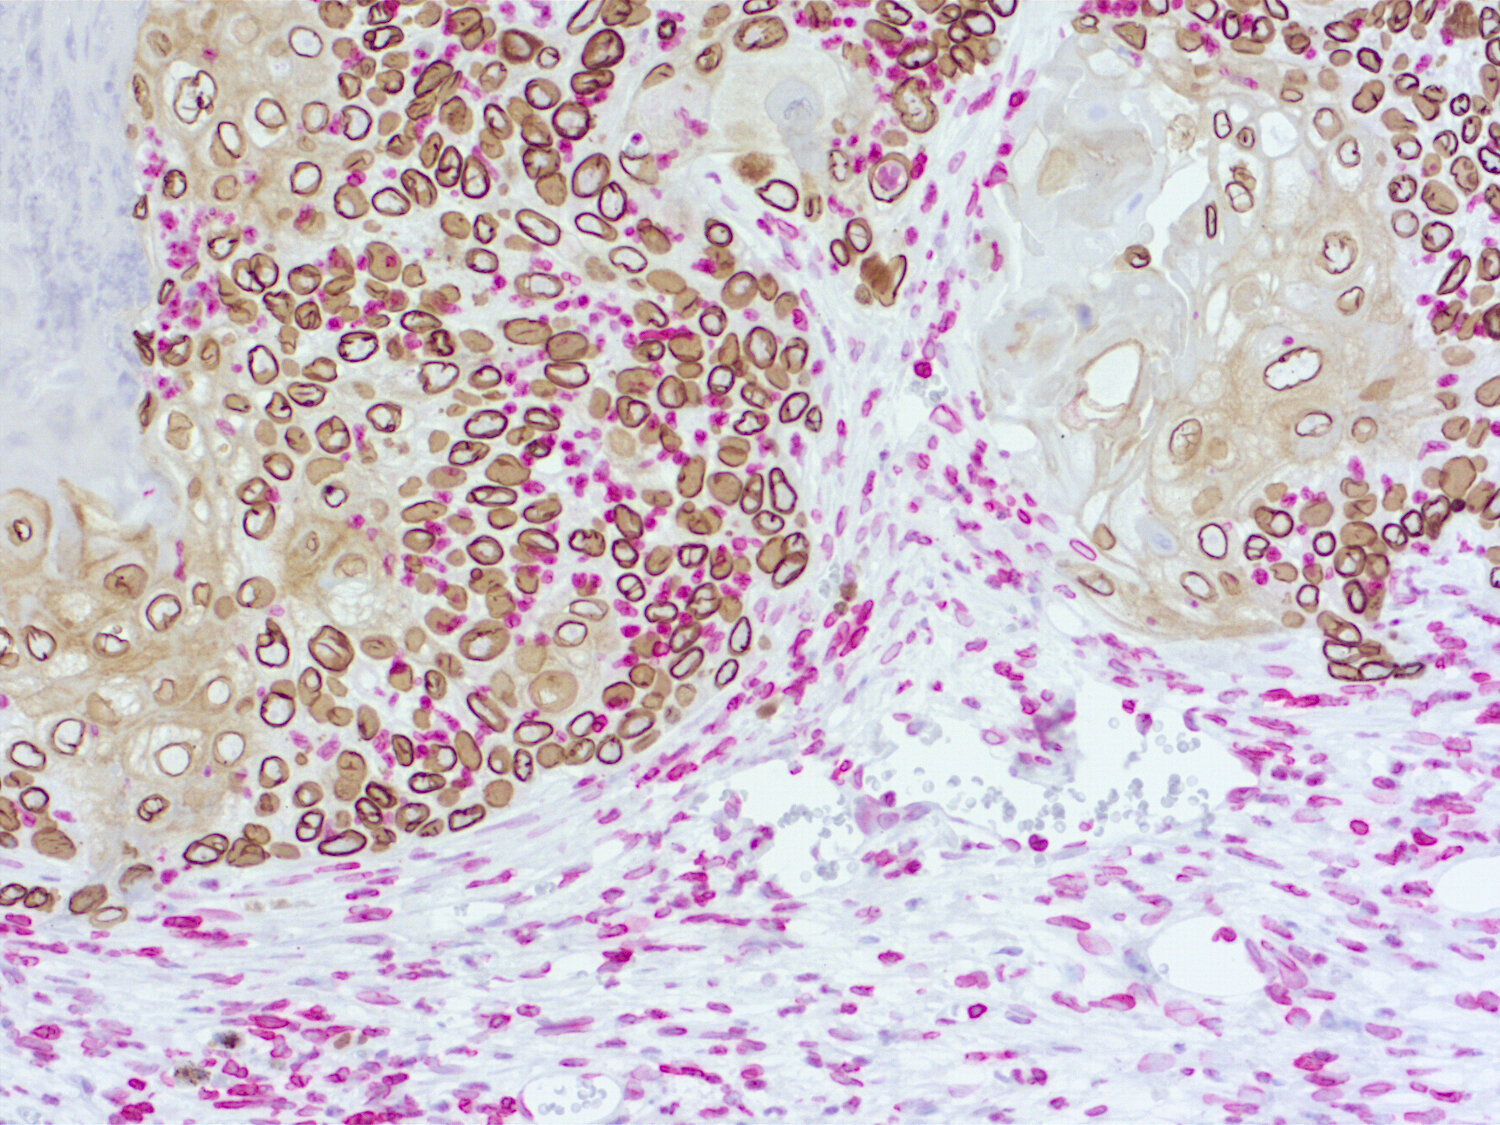

Immunohistochemical doublestaining of patient-derived pancreas cancer model

Figure 3b: Immunohistochemical doublestaining of patient-derived pancreas cancer model using rabbit anti-human Ki67 (cat.no. HS-398 003; AP-RED, red color) and rat anti-mouse Ki67 (cat.no. HS-398 117; DAB, brown color). Nuclei were counterstained with haematoxylin.